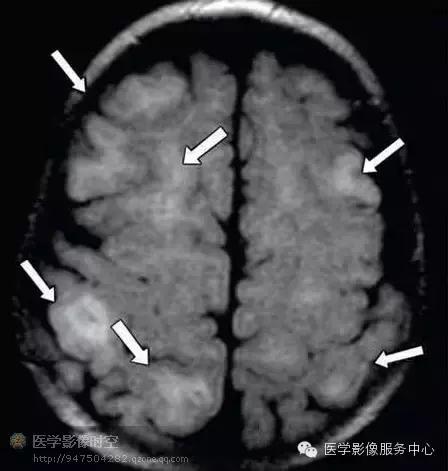

目前的影像学检查方法,包括磁共振成像,磁源成像,或者PET尚不能可靠的鉴别轻度皮质发育不良,局部皮质发育不良Ⅰ型和Ⅱ型(图1-6)。但是,如果发现皮层下T2高信号,尤其是延伸到侧脑室,常常是ⅡB型(图2)。目前认为T2高信号是髓鞘化程度低造成的,而非气球样细胞所致。其它的局部皮质发育不良的典型磁共振成像表现包括局部皮质增厚,灰白质界限模糊,灰质高信号(图6)。

图5 10月男孩,先天性癫痫,Ⅱ型局部皮质发育不良。

图5a 横断T2WI显示右顶叶灰质局部皮层增厚(箭)

图5b横断T1WI显示灰白质交界区模糊(箭)

图5c横断扩散张量成像显示胼胝体膝部窄小(箭),提示髓鞘化程度低。

图5d发作间期MR-PET融合图像显示大片低代谢区(箭)。病理学检查显示ⅡA型局部皮质发育不良。